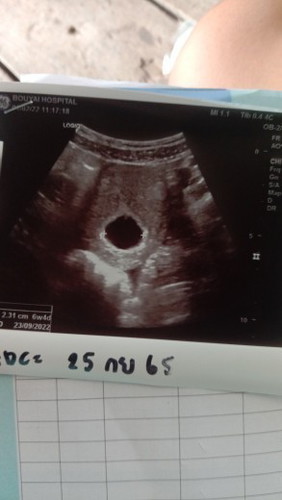

บ้านอื่นเจอตัวน้องกี่วีคกันค่ะ

มีแม่บ้านไหนเป็นกันบ้างค่ะบ้านนี้ 7w แล้วยังไม่เจอตัวน้องเลยค่ะเจอแต่ถุง

บ้านนี้เจอตัวน้องตอน 8w ค่ะ